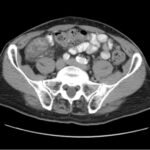

Small bowel diverticulitis is an uncommon subset of acute diverticulitis and can mimic many other intra-abdominal processes. As a result, imaging modalities such as ultrasound and computed tomography (CT) scan are especially important for timely recognition of diverticulitis and can expedite diagnosis and treatment and reduce complications. In the case described in this report, an 81-year-old male with history of esophageal cancer and recurrent diverticulitis with history of multiple bowel resections presented to the emergency department (ED) with right lower quadrant abdominal pain and constipation. Findings on ultrasound were suggestive of diverticulitis, and findings on CT of the abdomen and pelvis showed ileitis with phlegmon and micro-abscess suspicious for small bowel diverticulitis. ED providers should familiarize themselves with ultrasound findings of diverticulitis and be aware that diverticulitis can also present in the small bowel. Treatment of small bowel diverticulitis is similar to colonic diverticulitis.